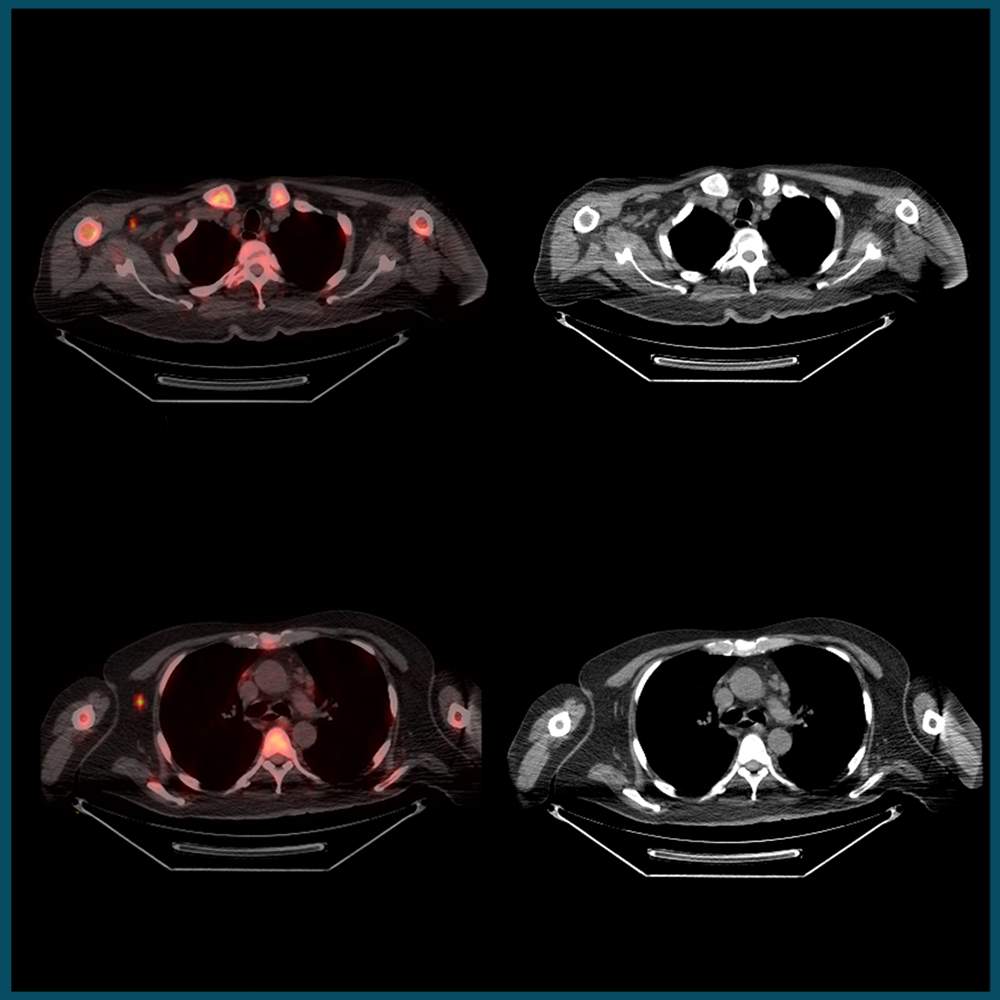

Artefacts in PET-CT

This course comprises of three tutorials where we discuss the clinical problems faced as a result of artefacts seen on FDG PET-CT imaging, and we’ll also cover some of the basic technical aspects behind the artefact and discuss some practical ways to minimise them.

There are three broad categories of artefacts seen on FDG PET-CT imaging. These are covered in the following learning modules.